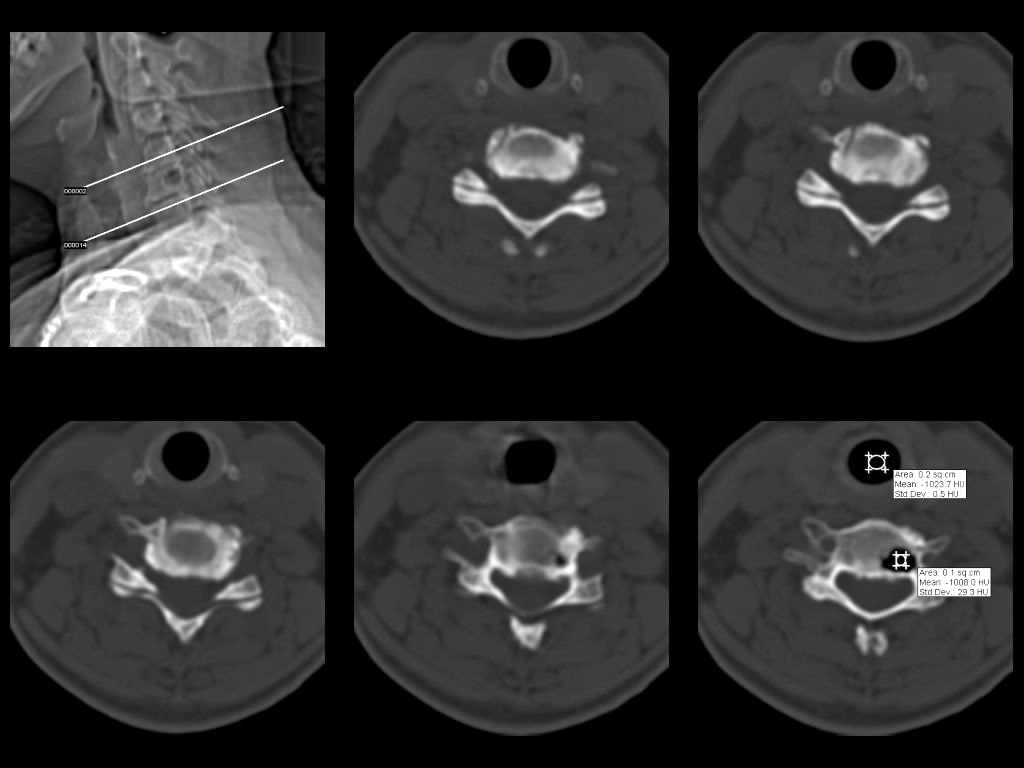

У женщины 49 лет, при рентгенографии шейного отдела в теле С6 выявлен участок деструкции.Часть N1 Больная находилась в неврологическом отделении с диагнозом энцефалопатия. Была проведена КТ тела С6, 26.12.2002 выявлен участок деструкции 0,9х1,2 см, плотность участка составляет -1022 ед.Н. аналогичная плотности воздуха в трахее.Возникает вопрос что это? Метастаз, киста,или какой то вредный анаэроб грызет тело позвонка?Через пол года 03.06.2003 произведено повторное исследование. Отмечается отрицательная динамика. Участок деструкции увеличился в размерах, увеличелась площадь разрушения задней поверхности тела С6.

Первые 2 серии снимков это от 2002г, вторые 2 серии от 2003 г. Относительно размеров, сообщю дополнительно все перермерю на томографе.

Размеры за 2002 год 1,2х0,9х1,2 мм

за 2003 1,3х0,9х1,2 мм. Но контур деструкции стал более неровный и внедрение в дужку С6 увеличелось.

Наличие выраженных дистрофических изменений, а также сообщение полости в теле позвонка С6 с полостью межпозвонкового диска в сегменте С5-С6, а также наличие газа в полости межпозвонкового диска С5-С6 спереди, на границе фиброзного кольца и пульпозного ядра (3-й слева срез в нижнем ряду на второй из представленных КТ) делает диагноз остеохондроза, осложненного вакуум-феноменом и прорывом газа в полость тела позвонка с формированием воздушной кисты (пневмкисты) несомненным.

Характер процесса не вполне ясен. Учитывая скопление газа на фоне тела

позвонка, с наибольшей вероятностью - "вакуум-феномен" в следствии

дегенерации межпозвонкового диска. Наложение газа на образование в теле

позвонка (гемангиома?) создает затруднение в диагностике (по-видимому

сочетание двух процессов). Желательно МРТ исследование. Если возможно,